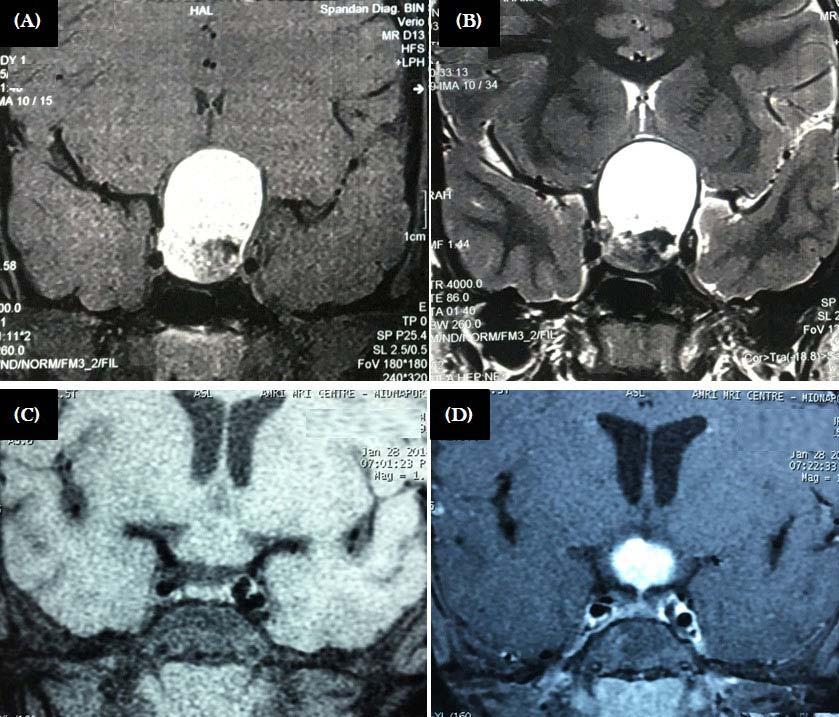

Majority of the patients had abnormal appearances of the HP region on MRI (Table 5) (Figs 1&2). Empty sella with varying thickness of the remaining pituitary tissue was the commonest abnormality noted (28 patients, 52.8% of the cohort). Only 3 patients (5.66%) had apparently normal looking HP region. Hypophysitis was diagnosed retrospectively in 1 lady with ES, whose previous MRI was consistent with hypophysitis11. One male with hypophysitis

Viper bite (n=16) Partial empty sella: 14; hypoplastic pituitary: 1; normal HP region: 1

Sheehan’s syndrome (n=13) Partial empty sella: 12; hypoplastic pituitary: 1

Pituitary macroadenoma (n=9) Sellar mass with/without supra & parasellar extension and heterogenous contrast enhancement

Sequel of pituitary Enlarged sella with residual surgery (n=3) tissue and fibrotic changes with deviation of stalk: 3

Craniopharyngioma (n=1) Sellar and suprasellar mass with mixed solid and cystic components and calcification

Hypothalamic mass (n=1) Isointense mass in T1 weighted MRI with intense contrast enhancement

Hypophysitis (n=4)

Transcription factor

Diffuse enlargement of the pituitary with stalk thickening and rapid, intense, and homogenous contrast enhancement:3; partial empty sella: 1

Hypoplastic pituitary: 3; Absent defect (n=3)pituitary stalk & ectopic posterior pituitary bright spot: 1

Idiopathic intra-cranial Partial empty sella with protruded hypertension (n=1) optic nerve head inside orbit and dilated optic nerve